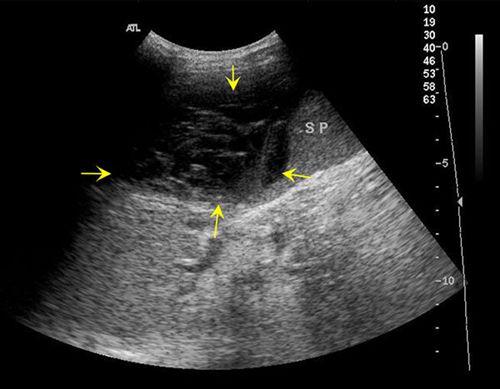

通常情况下,可以用彩色多普勒超声诊断仪来诊断是否发生脾破裂或鉴定脾脏受损程度。这是一种非侵入性检查,较常用,能显示破碎的脾脏,较大的脾包膜下血肿及腹腔内积血。